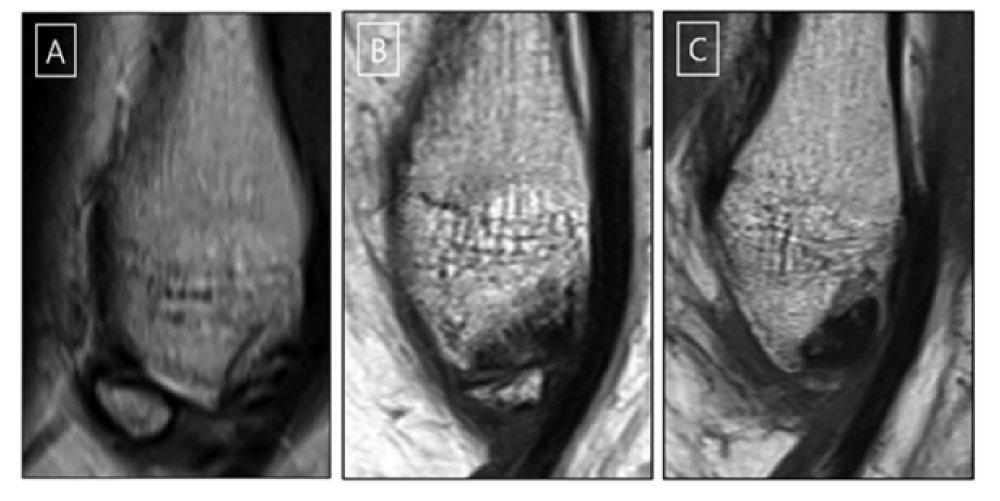

연구에 따르면, 참여한 만성 족관절 불안정증 환자 3명 중 1명은 비골하부골이 관찰됐다. 비골하부골은 인대가 손상될 때 함께 떨어져나갔지만 회복 과정에서 봉합되지 못한 뼛조각이다. 관찰된 뼛조각의 80%는 타원형이었으며 크기도 비교적 컸다.